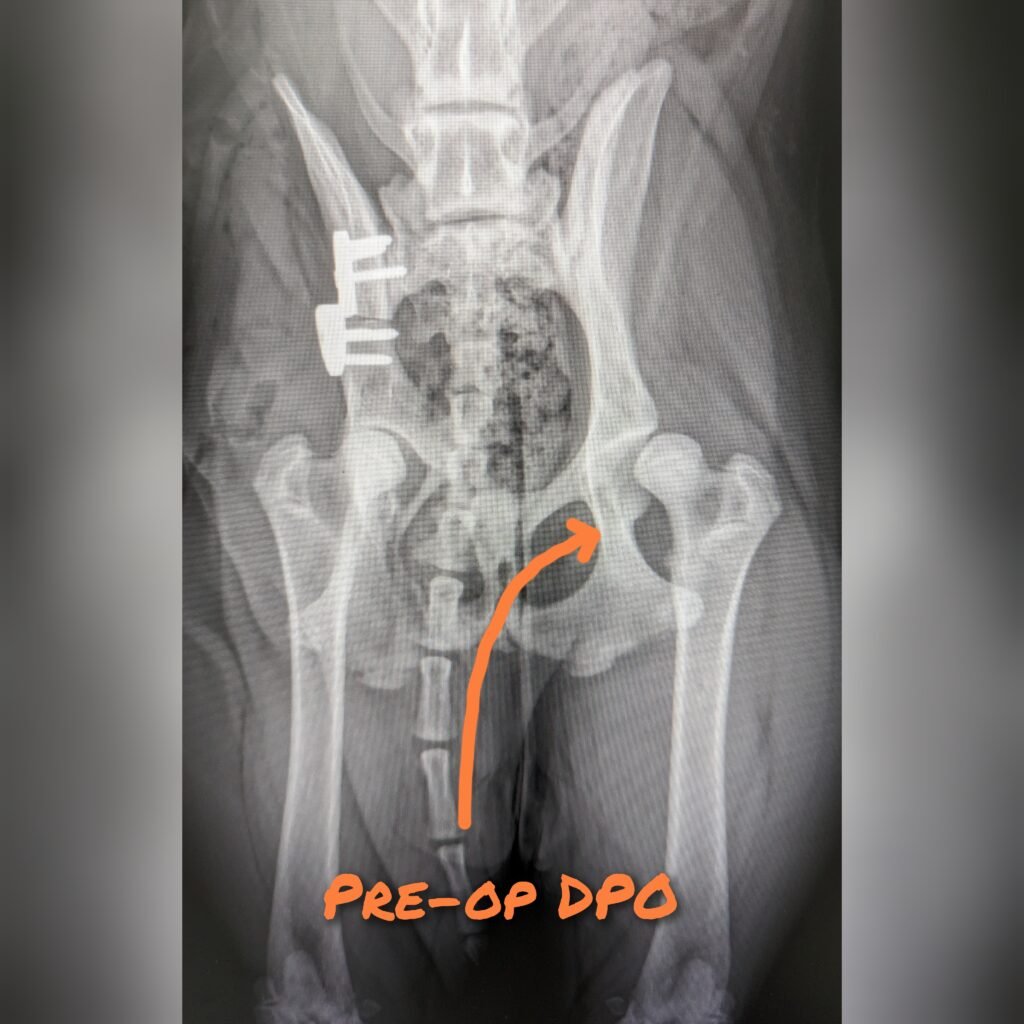

This surgery is appropriate for young dogs (8-12months old) with dysplasia but without osteoarthritis changes. This means that there is a window of opportunity for this surgery and if the dog develops arthritis or becomes too old, it will be too late to do this surgery.

Procedure involves sawing free the ill-fitting acetabulum from the rest of the pelvis, reposition the acetabulum piece for a tighter fit on the femoral head, and then stabiles the pelvic bone and acetabulum piece with plate/screws.

This procedure is much more involved and traumatic compare to JPS therefore early intervention is highly recommended if hip dysplasia was detected